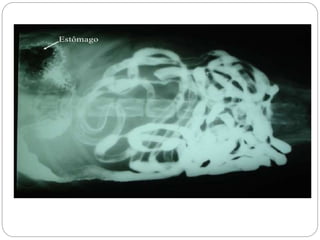

Radiografias